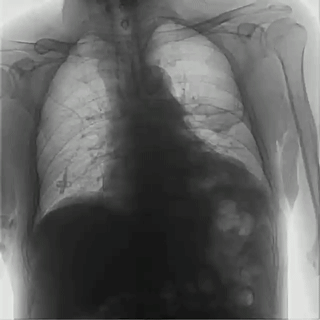

胸透影像

動(dòng)態(tài)平板DRF通過(guò)可視化功能進(jìn)行動(dòng)態(tài)觀察,影像清晰流暢,能夠捕捉到呼吸過(guò)程中肺部的細(xì)微變化,有助于醫(yī)生觀察肺部的運(yùn)動(dòng)和擴(kuò)張情況,尤其是在診斷哮喘、慢性阻塞性肺?。?/span>COPD)等疾病時(shí),對(duì)肺功能的評(píng)估更加準(zhǔn)確。同時(shí),通過(guò)多角度的動(dòng)態(tài)觀察,可以幫助醫(yī)生更加全面地評(píng)估呼吸系統(tǒng)疾病,對(duì)于一些在靜態(tài)影像中不易察覺(jué)的病灶,動(dòng)態(tài)平板DRF能夠通過(guò)連續(xù)的影像捕捉到細(xì)微變化,從而降低漏診和誤診的風(fēng)險(xiǎn)。動(dòng)態(tài)平板DRF成像速度快,醫(yī)生能夠即時(shí)觀察并分析呼吸系統(tǒng)的動(dòng)態(tài)變化,提高診斷速度,對(duì)于需要快速診斷的急性呼吸系統(tǒng)疾病諸如氣胸、肺栓塞尤為有利。